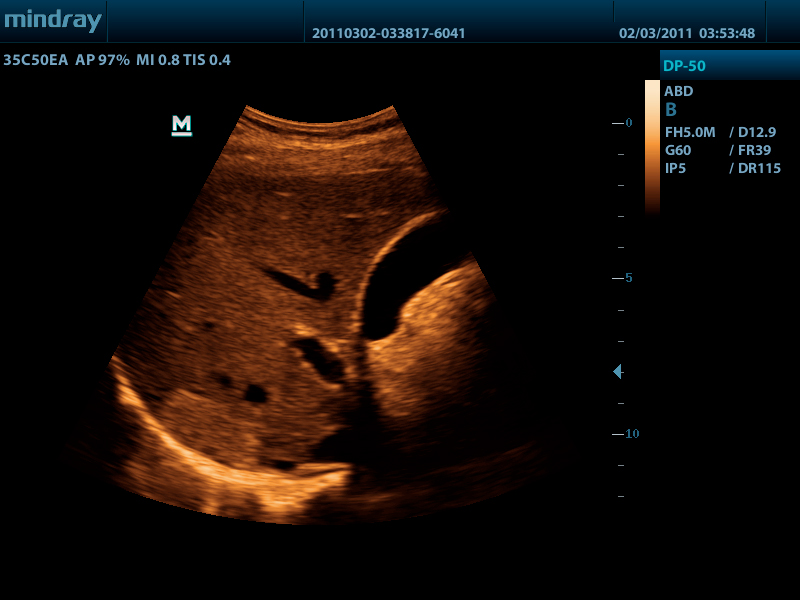

УЗ-сканер DP-50 Color представляет собой новое поколение ультразвуковых систем с цветных доплером компании Mindray. Он оснащен передовыми технологиями визуализации, обеспечивающими более глубокое проникновение и быстрое получение изображений при более высоком разрешении. УЗ-сканер DP-50 color отлично подходит для всех клинических ситуаций благодаря своей новой высокотехнологичной конструкции, повышенной мобильности и удобству эксплуатации.

- Псевдоокрашивание

PSHI (гармоническая визуализация с фазовым сдвигом) Изолированная гармоническая визуализация для улучшения контрастного разрешения, обеспечивающая более четкое изображение с превосходным пространственным разрешением и меньшим уровнем шума.

iBeam Позволяет использовать несколько углов сканирования для формирования единого изображения, что приводит к увеличению контрастного разрешения и улучшению визуализации.

iClear Позволяет улучшить качество изображения, основываясь на автоматическом распознавании структур.

- Конвексный датчик 35C50EA, 1.7 - 6.0 МГц, радиус кривизны 50 мм